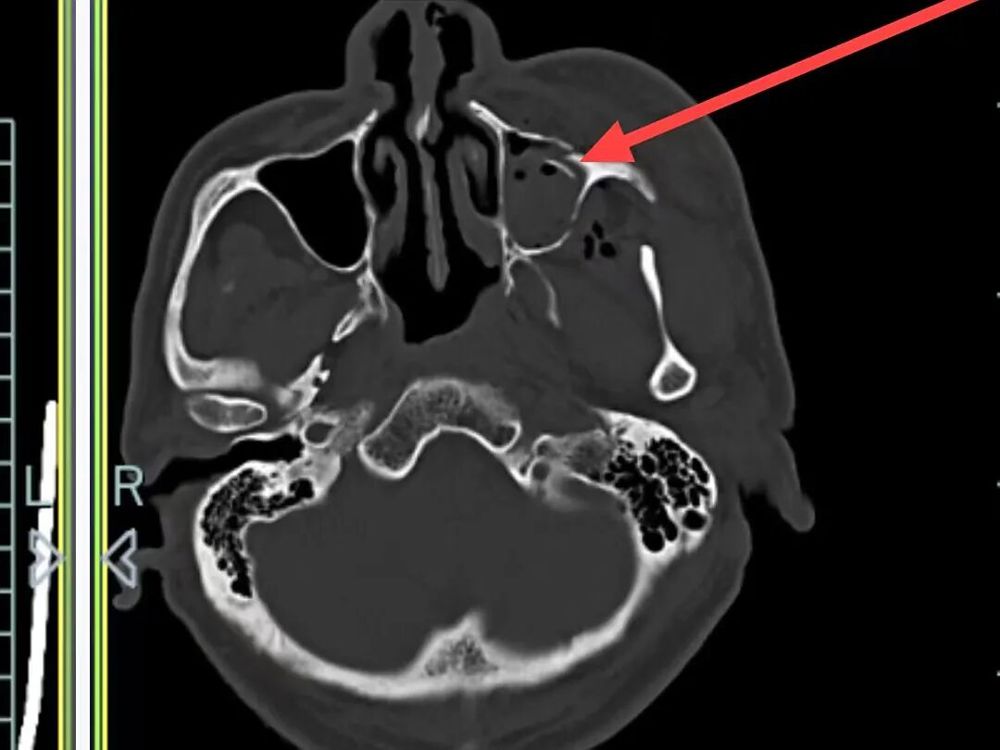

医院快速开通绿色通道并完善一系列检查后,诊断结果令人揪心:孙先生患有重型闭合性颅脑损伤,包括多发性创伤性脑出血、右侧颞部创伤性硬膜下出血、创伤性蛛网膜下腔出血以及脑震荡,同时合并多处骨折及软组织挫裂伤。

硬膜下出血、蛛网膜下腔出血和多发性创伤性脑出血

外侧壁、左眼眶外侧壁骨折、左侧颌面部软组织肿胀,软组织内积气

左侧颞骨、左侧颧弓、左侧上颌窦前壁骨折